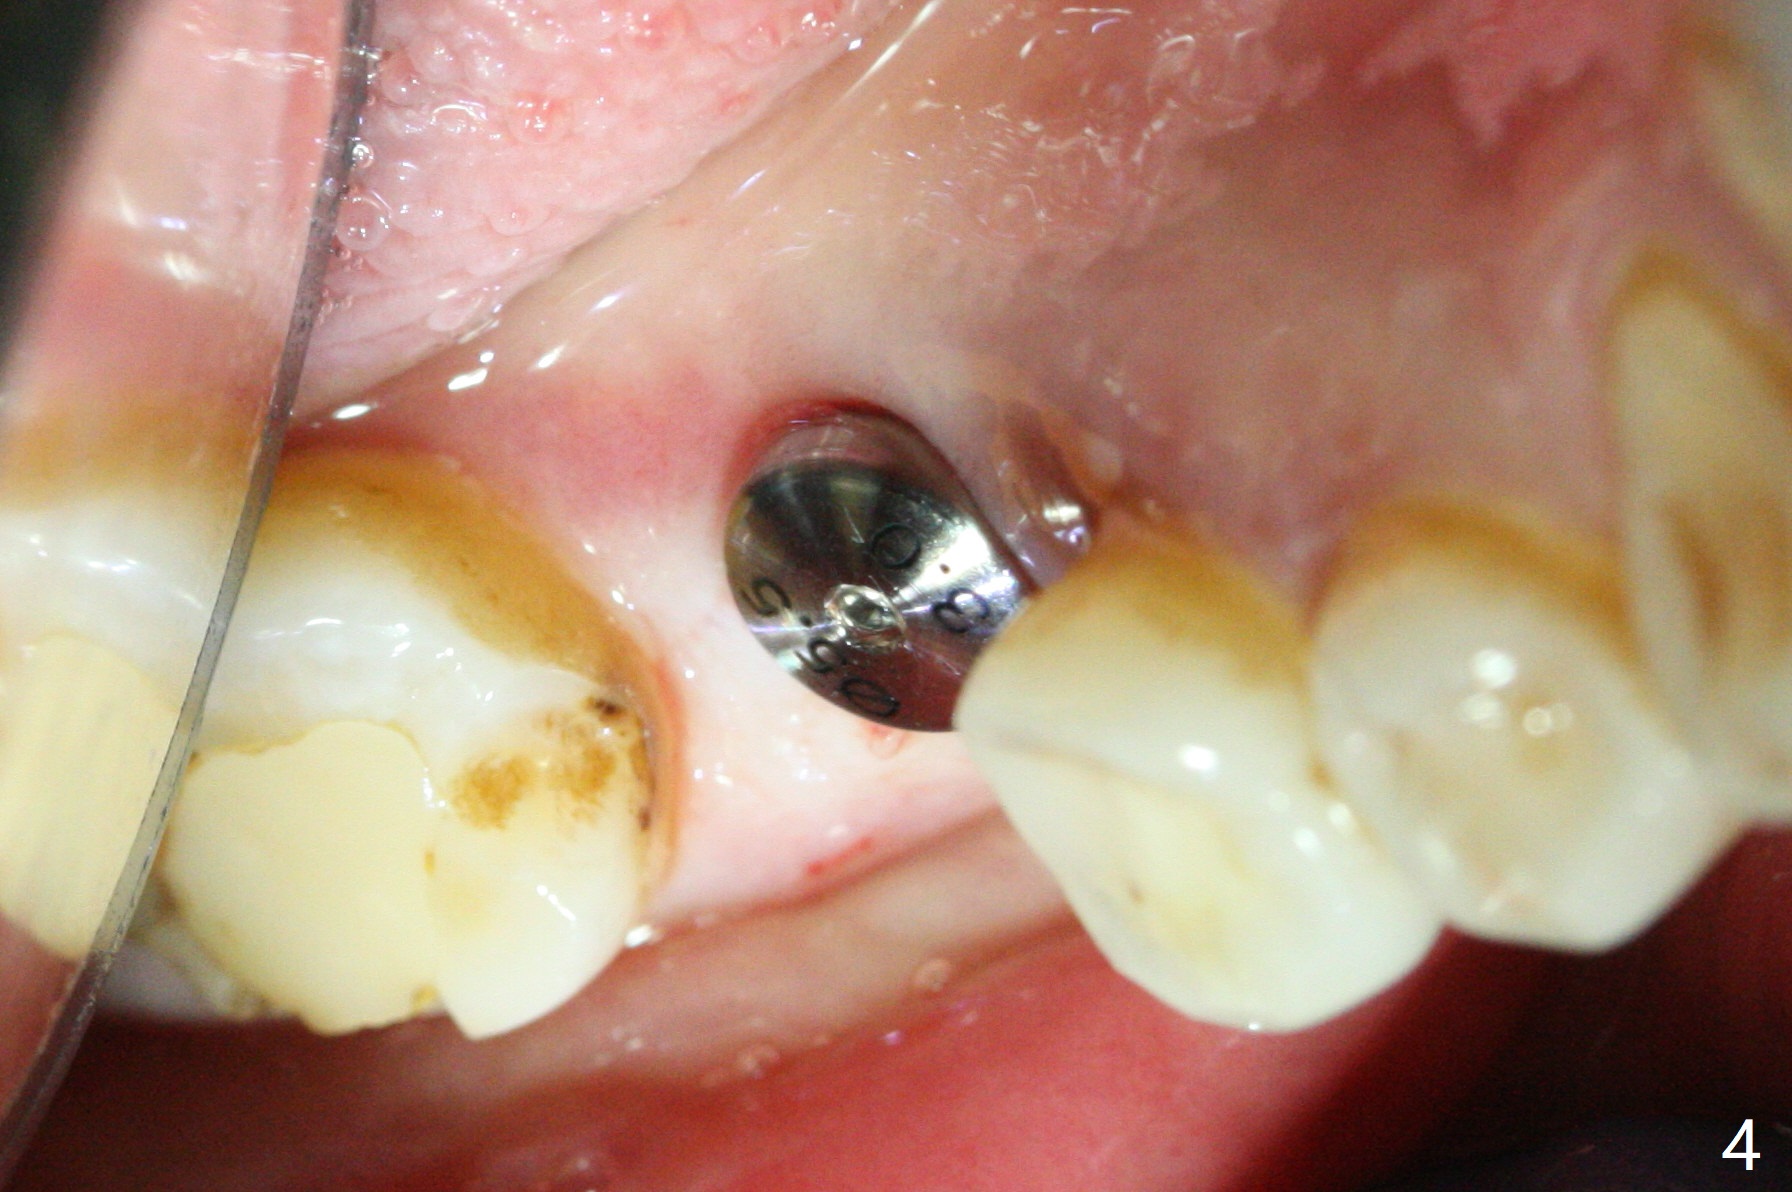

A 5x10 mm implant is placed at #30 with a surgical guide (Fig.1 *) in 10 minutes. The most amazing part of this surgery is that the guide allows you to place the implant at the precise level care-free (~ 1 mm subcrestal, Fig.2,3). Everything happens so quick that when a 5.5x3 mm healing abutment is placed (Fig.4), you are pleased to feel that the implant is stable (Fig.5). You could not ask for anymore. The fearful patient reports no postop pain. The implant is placed as planned (Fig.6, overlap image provided by the guide designer, Jennifer). The patient returns for impression nearly 2 months postop (Fig.7,8). It appears that the implant has osteointegrated without bone loss (Fig.7). The soft tissue is healthy around the just placed cementation abutment (Fig.8 (5.2x4(2) mm)). When the permanent crown is seated initially 2.5 months postop, the mesial contact is slightly tight and the occlusion is high. Bitewing shows the distal open margin (Fig.9 >). After mesial contact adjustment, the patient feels that the occlusion is better. With further occlusal adjustment, the crown is cemented without distal open margin (Fig.10). The patient returns to her home country for 3 months. The implant is doing well 3.5 months post cementation; impression is taken for #14 surgical guide.